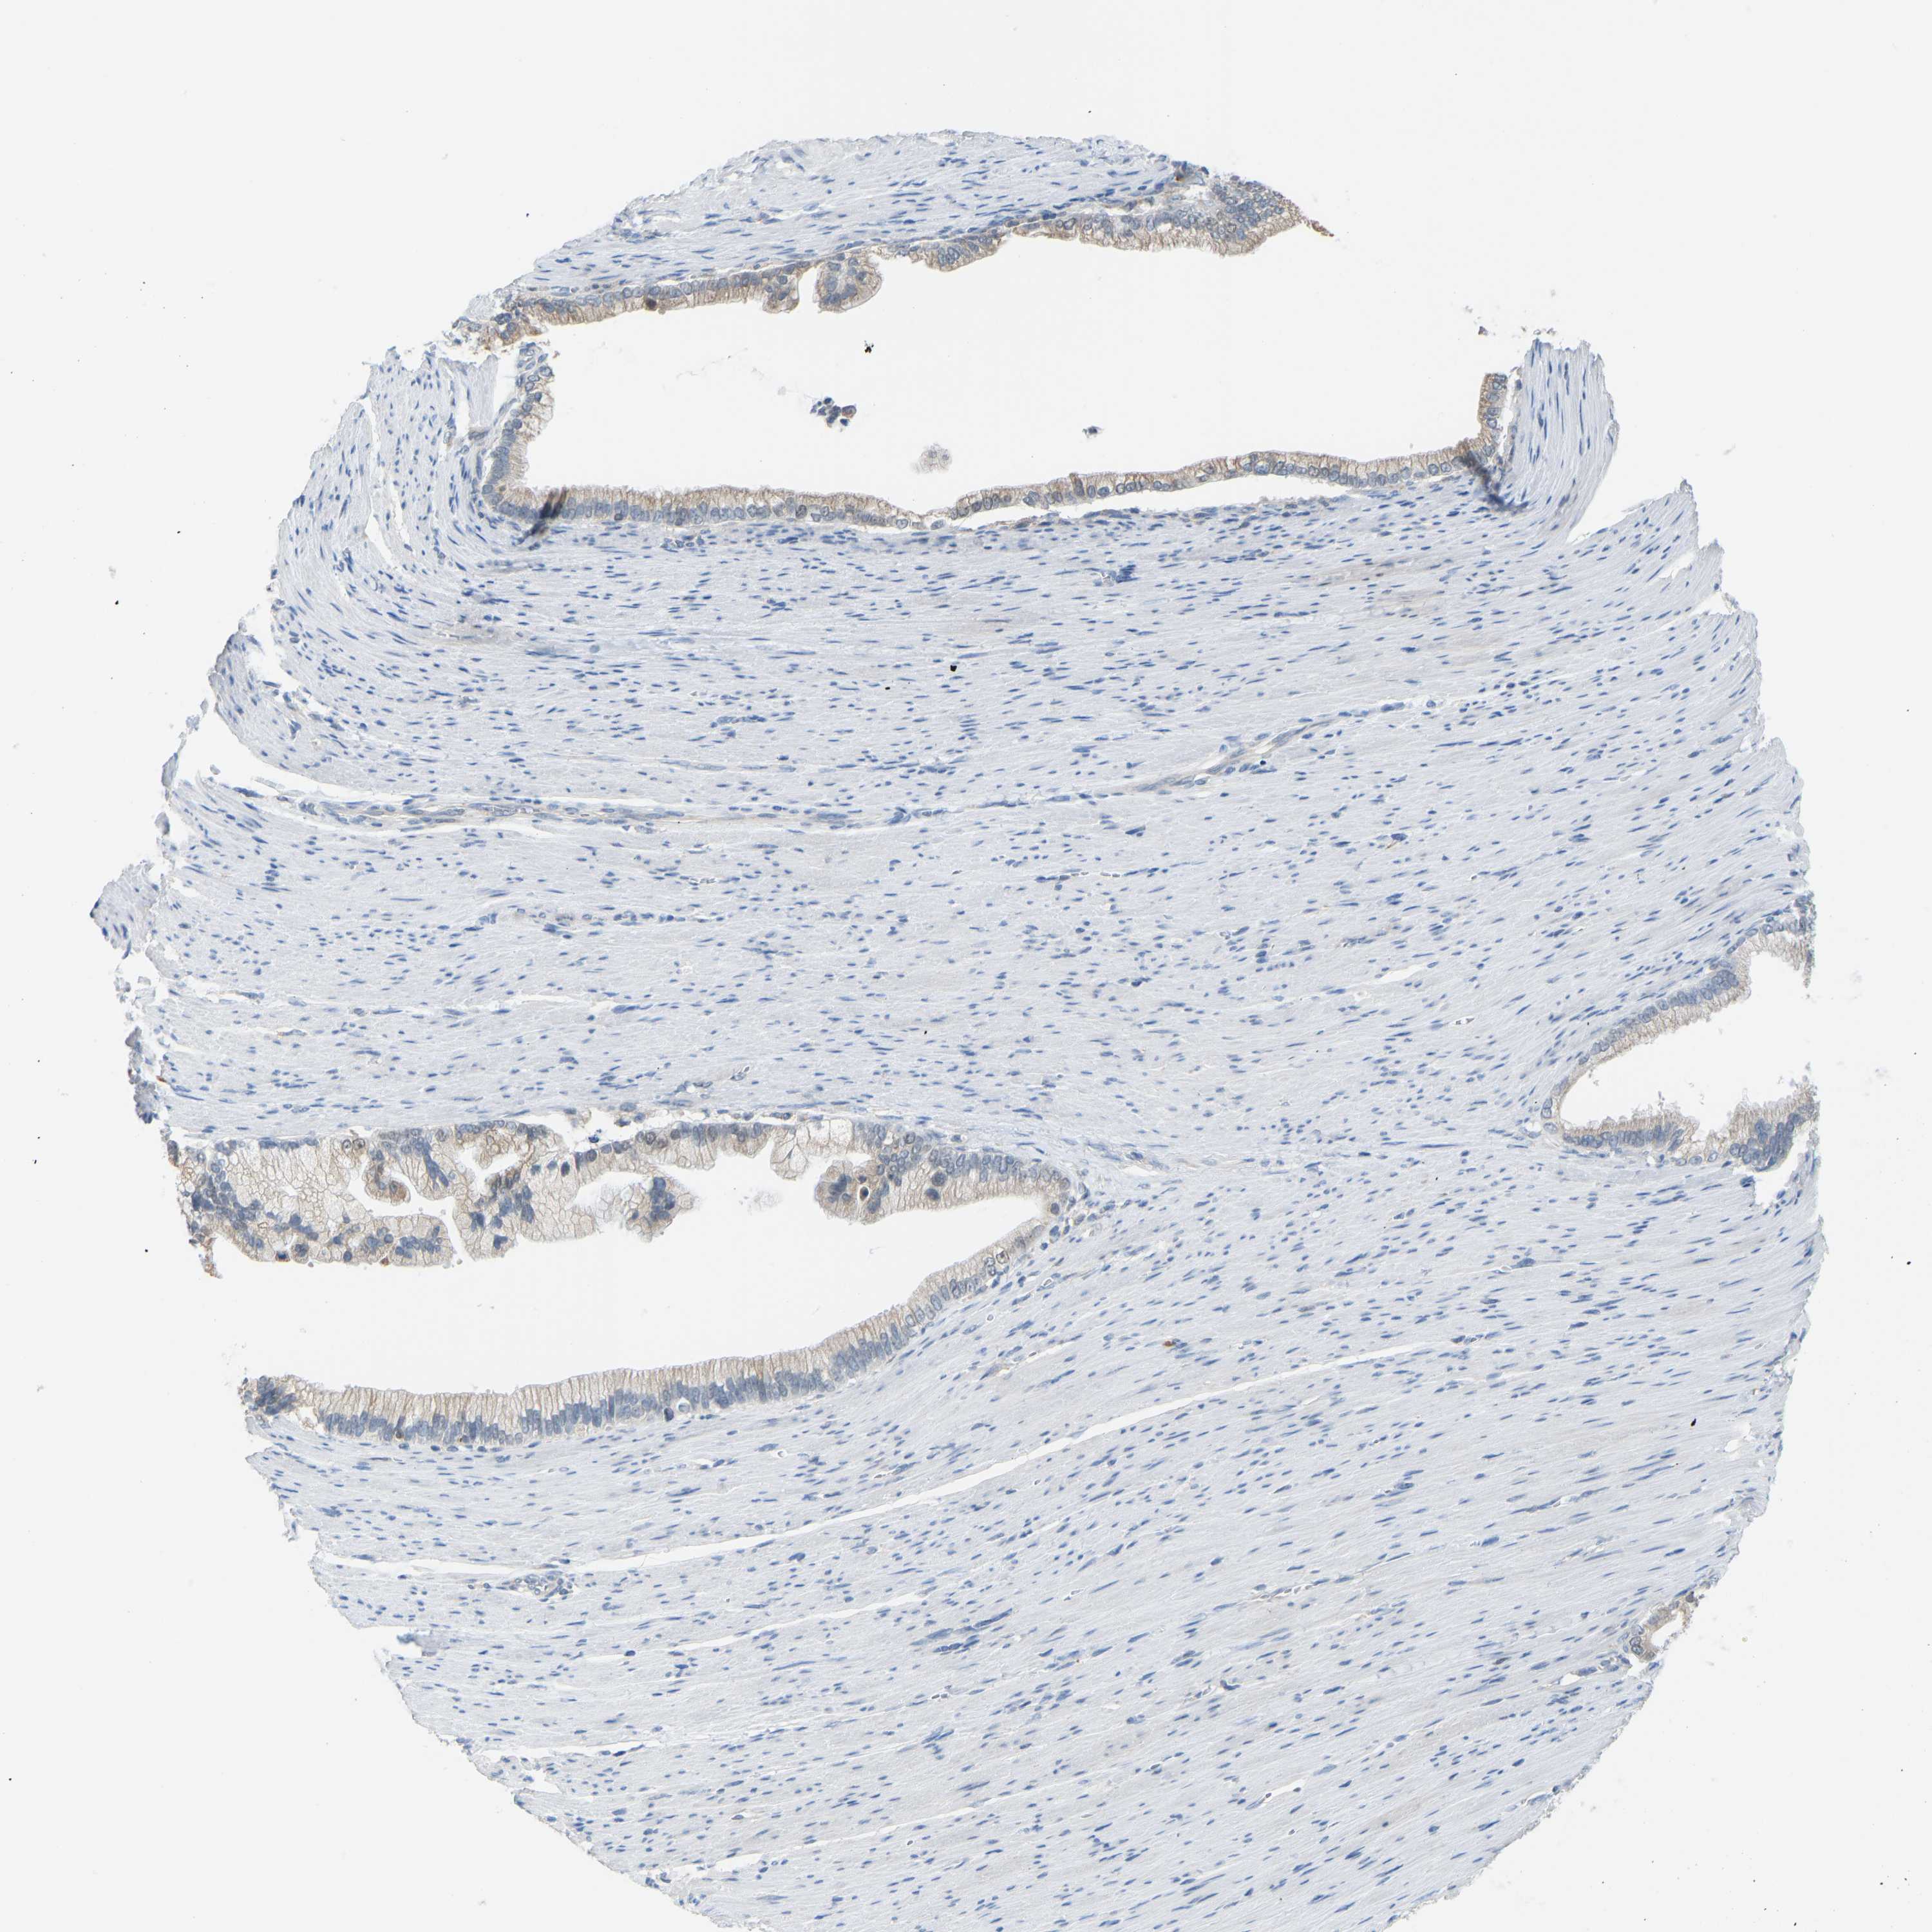

PANCREATIC CANCER - Protein expressioni

A mouse-over function shows sample information and annotation data. Click on an image to view it in a full screen mode. Samples can be filtered based on level of antibody staining by selecting one or several of the following categories: high, medium, low and not detected. The assay and annotation is described here.

Note that samples used for immunohistochemistry by the Human Protein Atlas do not correspond to samples in the TCGA dataset.

Antibody stainingi

Antibody staining in the annotated cell types in the current human tissue is reported as not detected, low, medium, or high, based on conventional immunohistochemistry profiling in selected tissues. This score is based on the combination of the staining intensity and fraction of stained cells.

Each image is clickable and will lead to virtual microscopy that enables deeper exploration of all samples and also displays staining intensity scores, fraction scores and subcellular localization as well as patient and tissue information for each sample.

Antibody HPA000660

Antibody HPA017929

Staining

High

Medium

Low

Not detected

Intensity

Strong

Moderate

Weak

Negative

Quantity

>75%

75%-25%

<25%

None

Location

Nuclear

Cytoplasmic/membranous

Cytoplasmic/membranous,nuclear

Adenocarcinoma, NOS